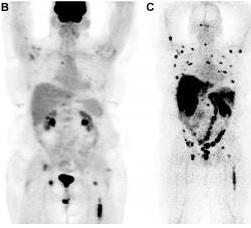

Il s'agit d'un nouvel agent d'imagerie (Zr-89-desferrioxamine-IAB2M ou Zr-89-Df-IAB2M), an anti-PSMA (prostate-specific membrane antigen) capable de détecter rapidement et avec précision les métastases du cancer de la prostate, même dans les régions où la détection était auparavant difficile. L'étude montre son efficacité dans le ciblage à la fois les os et des lésions des tissus mous. L'agent est « imagé » plus rapidement que d'autres anticorps d'imagerie ciblant le PSMA en raison de sa petite taille (minibody) et s'avère ici sans danger pour les patients. L'agent s'attache à la surexpression de l'enzyme PSMA à l'extérieur des cellules de cancer de la prostate où les particules émises à partir du site sont ensuite détectées par tomographie par émission de positons (PET scan). Il permet ainsi de détecter et d'évaluer les métastases osseuses qui sont les plus difficiles à évaluer avec les méthodes standard.

18 patients ont été imagés avec ce nouvel agent ainsi qu'avec les méthodes d'imagerie classiques (tomodensitométrie, IRM, scintigraphie osseuse moléculaire ... Les sites suspects ont fait l'objet de biopsies. L'étude montre que la nouvelle technique permet de détecter les lésions squelettiques et nodales : les scans s'avèrent positifs chez 17 des 18 patients, avec des lésions osseuses ciblées chez 9 d'entre eux et des lésions des tissus mous chez 14 d'entre eux. Des résultats bien plus précis qu'avec les méthodes d'imagerie traditionnelles. Au total, ce nouveau mode d'imagerie a permis de détecter 147 lésions osseuses et 82 lésions de tissus mous ou nodales.

2016, doi: 10.2967/jnumed.116.176206 First-in-Human Imaging with 89Zr-Df-IAB2M Anti-PSMA Minibody in Patients with Metastatic Prostate Cancer: Pharmacokinetics, Biodistribution, Dosimetry, and Lesion Uptake (Visuel@Crédit: Neeta Pandit-Taskar, M.D., et Michael J. Morris, M.D., Memorial Sloan Kettering Cancer Center)